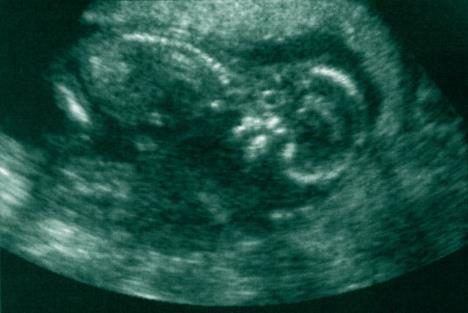

Napravili su ultrazvuk, ali prema proceduri, Džil nije smela da vidi snimke ni slike svog deteta. Kada je otišla na recepciju da plati za proceduru, Džil je dobila jasan znak od Boga da treba da pobegne iz tog mesta. Tamo, na njenom kartonu, jedna je od radnica slučajno ostavila sliku ultrazvuka njene bebe. Džil je videla svog sina, njegov nos, njegove ruke i noge, njegovu glavu i prstiće koji su tek nastajali. Znala je da ne može da nastavi dalje.

- Ovo nije u redu. Videla sam bebu na ultrazvuku. Moramo pričati o ovome, moramo otići odavde.